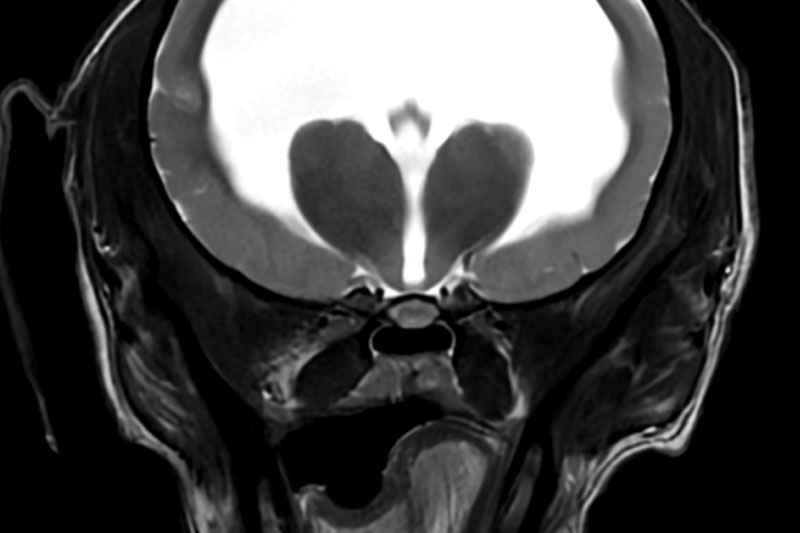

| 뇌/두개강 | 뇌종양, 뇌염, 수두증, 간질, 뇌출혈, 시신경 이상 등 |

뇌·척수 등 중추신경계 연부조직 변화 정밀 확인